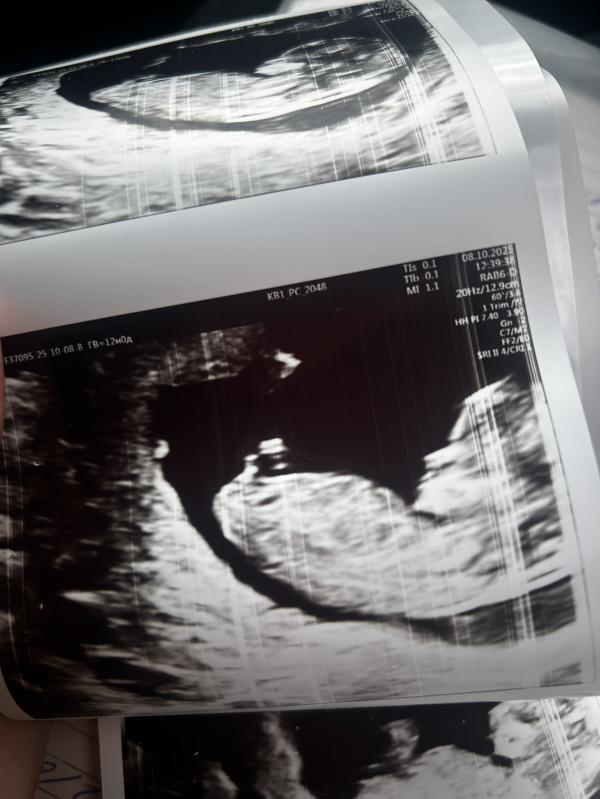

Прошла первый скрининг, все хорошо, ровно 12 недель, сказали мальчик🩵

Но назначили утрожестан два раза в день из за шейки 32, и шва 4, и риска преждевременных до 34 недели

Да мальчишечка 😇

Тут прям железобетонно мальчик🥹 видно